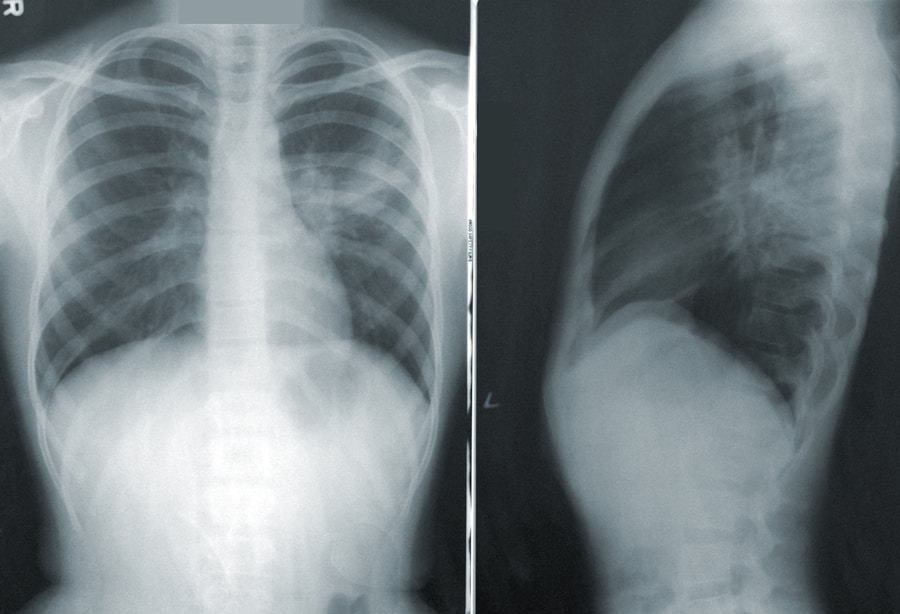

One of the most serious concerns is respiratory failure, which can occur if the muscles responsible for breathing become severely weakened. In such cases, patients may require mechanical ventilation to assist with breathing until they regain sufficient muscle strength.